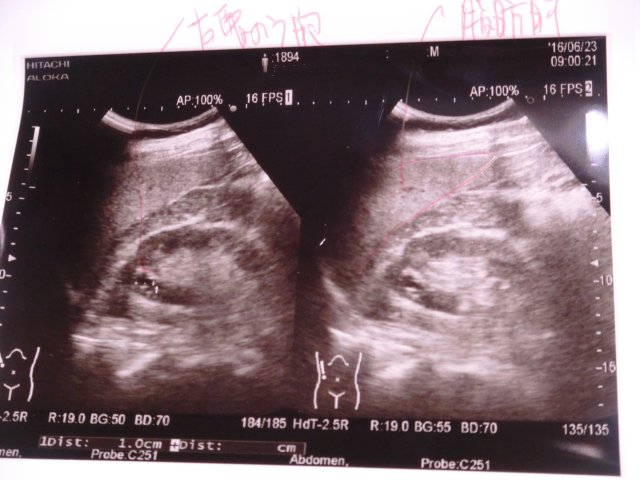

Cimg0190 胆のうの画像:胆のうポリープがあるって。

「胆のうポリープとは、胆のうの内面に出来る、隆起病変の総称で基本的には良性のものがほとんどで長期間に渡っておとなしい病気だけど、胆のうポリープの中には悪性のもの(胆嚢癌)があり、胆嚢ポリープと診断された場合は、専門の施設で精密検査を受けることをお勧めします。」

だって。